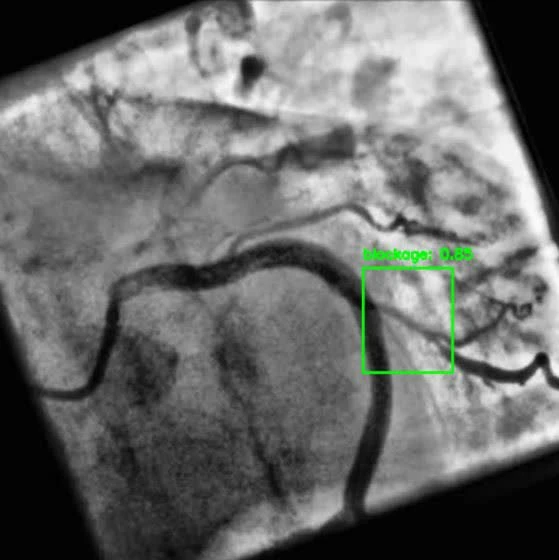

YOLOV8 for Real Time Coronary Blockage Detection